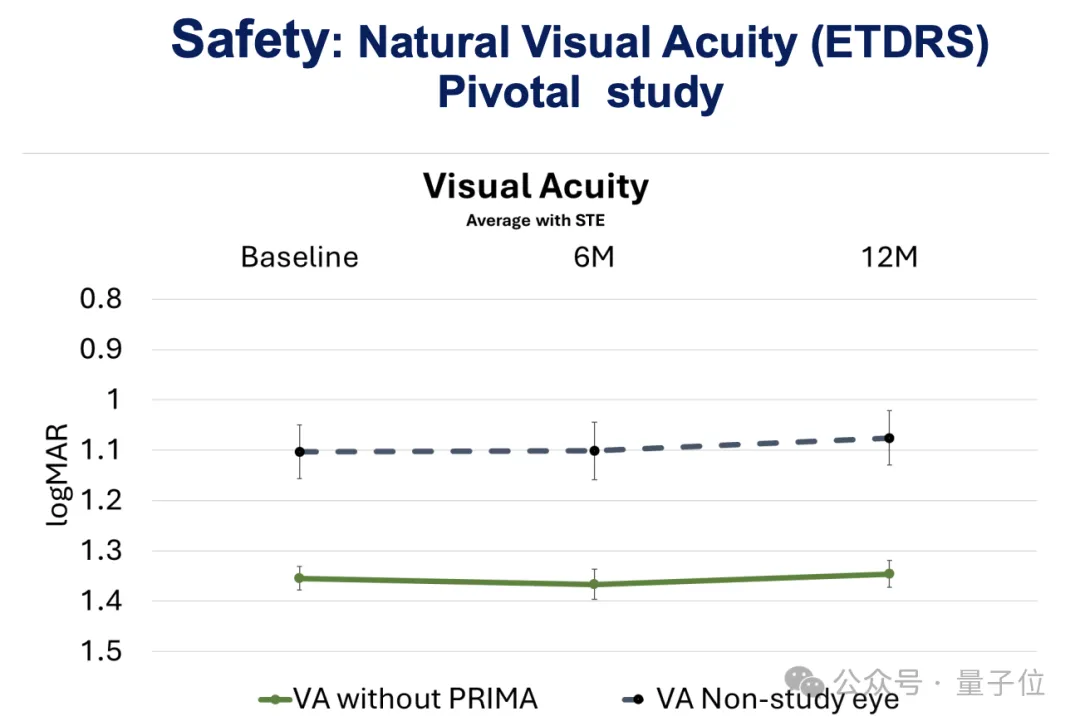

定量上看,研究者在植入后6个月和12个月时,对所有患者的视力通过logMAR评分进行了测量(logMAR为0表示视力正常,正值表示视力不佳),结果显示出了具有临床意义的改善:

而且患者不使用PRIMA时的平均自然视力在植入后保持稳定,说明了PRIMA植入物具有良好的安全性。